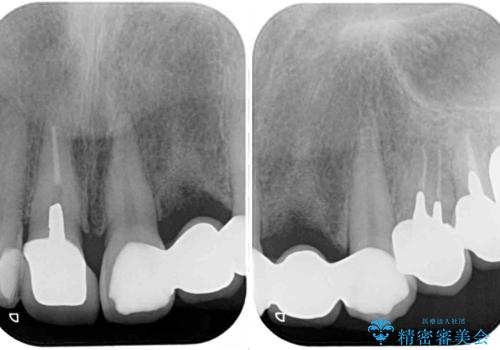

歯の裏側を一層だけ削り、接着力に頼ったブリッジを装着してはみたものの、案の定咬む力に負けて、接着が剥がれてしまっていました。

他にも、奥歯の銀歯の下にもむし歯が多くあり、痛みが生じていたため、根管治療などを行った上で、オールセラミッククラウンにて補綴治療することとしました。

前歯の裏側の接着面は、隙間ができていたことにより、汚れがたまるだけでなく、むし歯にもなっていました。